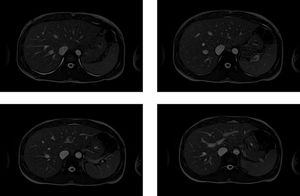

High resolution 2D True-FISP for the MR Imaging of the liver. True-FISP sequence provides high SNR and resolution but is not good for the characterization and differentiation of the pathology, due to its inherent T2/T1 contrast.